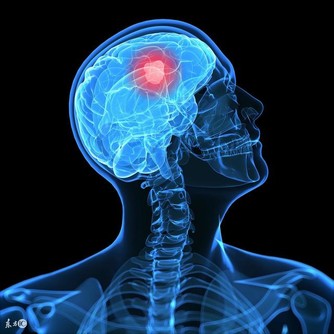

頸椎病本是中老年人的常見疾病,可是隨著年輕人的工作習慣等問題,不少人年紀輕輕就開始遭受頸椎病痛的折磨,白天辛苦工作一天,晚上頸椎還痛的睡不著。頸椎病可導致頸肩痛、頭暈頭痛、四肢無力等,嚴重者甚至出現肌肉萎縮、下肢痙攣、大小便失禁、癱瘓等,治療頸椎病刻不容緩。